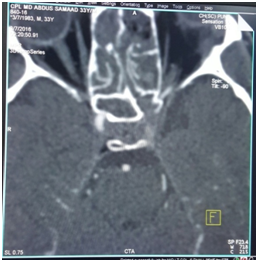

Patient was mobilized by 3rd postop day with support and intensive physiotherapy was started. By 5th day he started walking and by the end of a week his Power in limbs of right side improved. Post op regular every day endoscopic suction toileting of nasal cavity and PNS was done carefully so as to avoid any infection or crusts and to assess how clot is organizing over the injured part of Lt ICA in left sphenoid sinus (Figure 5). At 3weeks the clot was fully flushed with bony canal of ICA and almost became indistinguishable. MRI showed improvement in the circulation at the infarct areas. The patient regained all his motor functions by 4weeks and he could do all normal activities.

Figure 5 Organised clot 14 postoperative day.